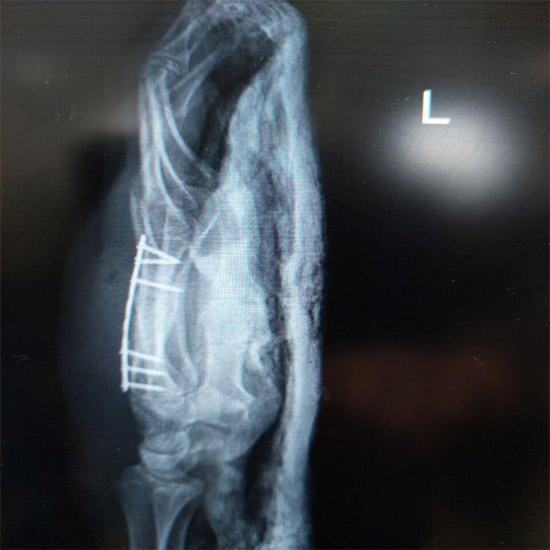

بخشی از نمونه کارها

نمونه کارهای قبل و بعد